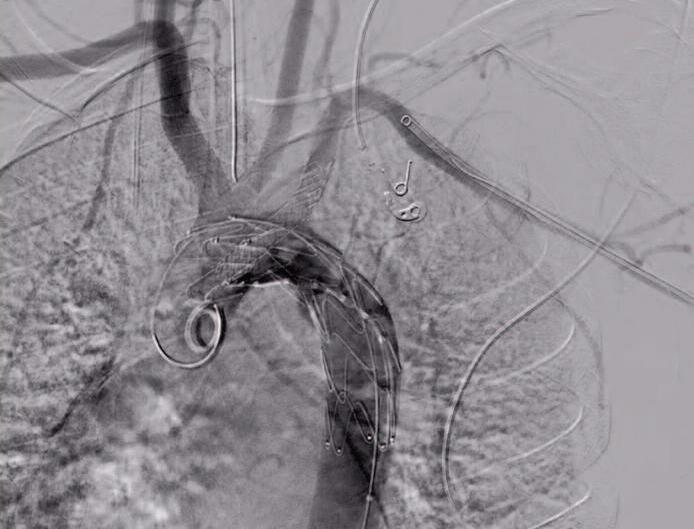

159 R i p a ra z i o n e t o t a l m e n t e e n d ova s c o l a r e d i u n a r o t t u ra dell’istmo aortico: caso clinico in un politrauma Totally endovascular repair of a traumatic aortic isthmic rupture:

a case report of a polytrauma patient

La rottura aortica rappresenta un'emergenza potenzialmente letale che può complicare un politrauma La stabilizzazione della lesione per via endovascolare costituisce un approccio terapeutico fattibile e rapido che consente di dedicarsi in un secondo momento alle altre lesioni ODDI F M , CARNEVALE R , FRESILLI M , IPPOLITI A